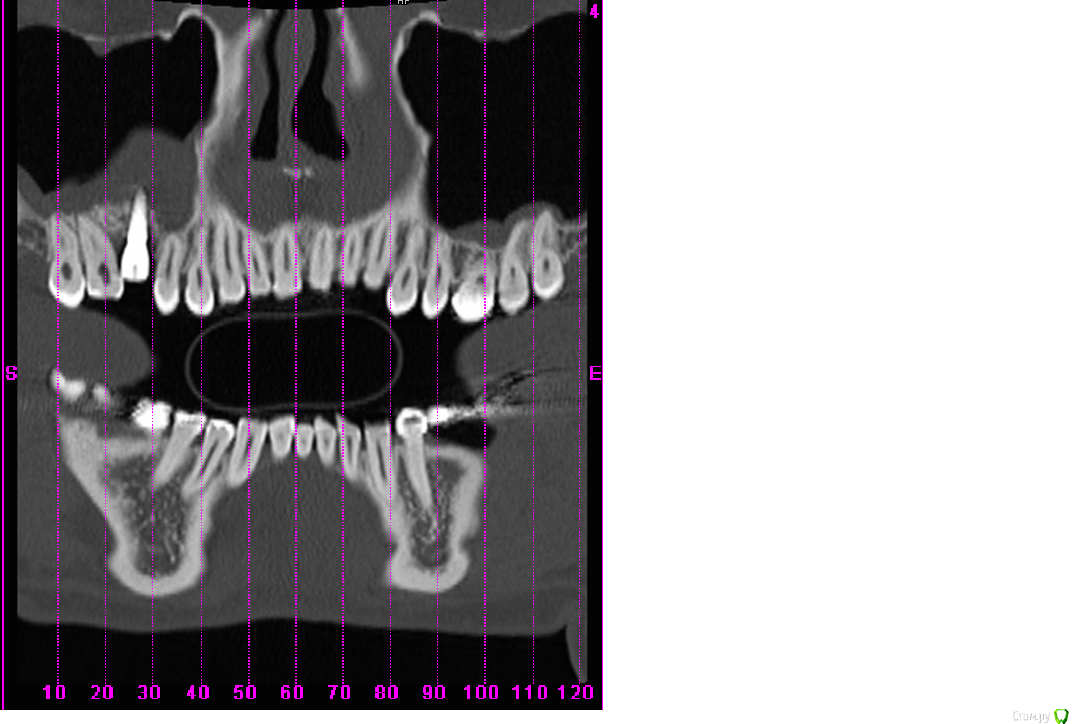

scrappy_coco Опубликовано 17 февраля, 2015 Поделиться Опубликовано 17 февраля, 2015 (изменено) Здравствуйте! После синус-лифтинга и костной пластики был установлен имплантат 6 зуб(6месяцев назад, настал момент протезирования, зашаталась 5ка рядом с имплантом, встал вопрос о удалении и имплантировании 5ки, всвязи со смещением и более этетичным видом сразу двух изготовленный коронок)решил проконсультироваться с другими врачами, которые диагностировали ассептический гайморит, нужно удалять имплантат, мой врач говорит, что все нормально, утолщение слизистой- результат манипуляций с областью, гайморит в состоянии ремиссии ) . Симптоматики гайморита нет. Кто прав? Рассмотрите, пожалуйста, ситуацию в прилагающихся скринах . Изменено 17 февраля, 2015 пользователем scrappy_coco Ссылка на комментарий

Mane Опубликовано 17 февраля, 2015 Поделиться Опубликовано 17 февраля, 2015 (изменено) Гайморита нет Изменено 17 февраля, 2015 пользователем Mane Ссылка на комментарий

scrappy_coco Опубликовано 20 февраля, 2015 Автор Поделиться Опубликовано 20 февраля, 2015 Гайморита нетимеет ли данная конструкция перспективу, не разовьется ли гайморит в последствии при нагрузке Ссылка на комментарий

Mane Опубликовано 22 февраля, 2015 Поделиться Опубликовано 22 февраля, 2015 имеет ли данная конструкция перспективу, не разовьется ли гайморит в последствии при нагрузкеОртопедическая конструкция при адекватной гигиене к гаймориту не приведет. Удалить 15 - глупость. Компромисная эстетика - это если приоочить зубы 17 и 15 с контактных сторон и сделать в этих условиях коронку на имплант. Идеальный план:Планирование ортодонтического леченияВозможно удаление имплантаОртодонтич дечениеВозможно новая имплантацияПротезирование Ссылка на комментарий